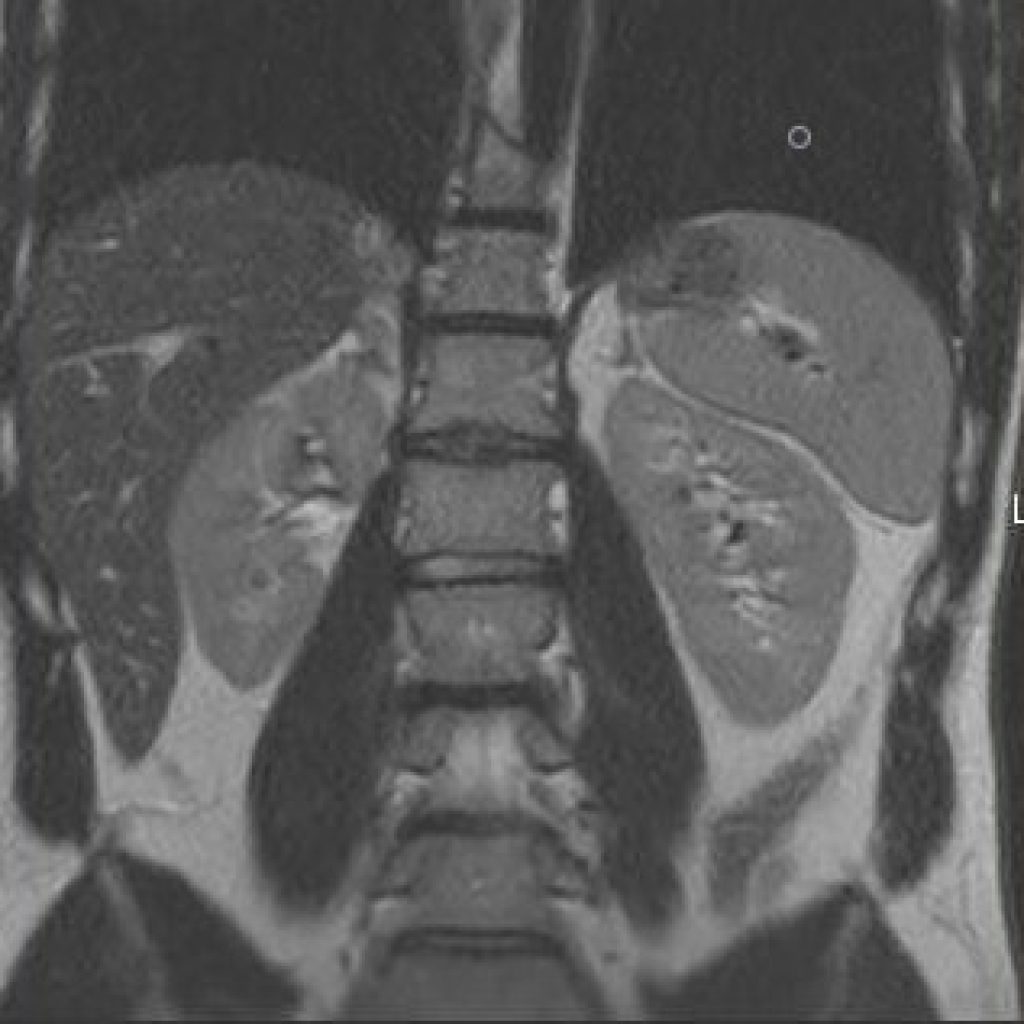

Ce type d’exploration s’intéresse au foie, aux surrénales, aux reins, au pancréas, à la rate et au péritoine

Quelques exemples :

– recherche d’une surcharge en fer du foie,

– quantification d’une stéatose, suivi des fibroses intra-hépatiques,

– cartographie des lésions cancéreuses et suivi de leur réponse sous traitement,

– recherche de calculs au sein des voies biliaires ou de la vésicule.